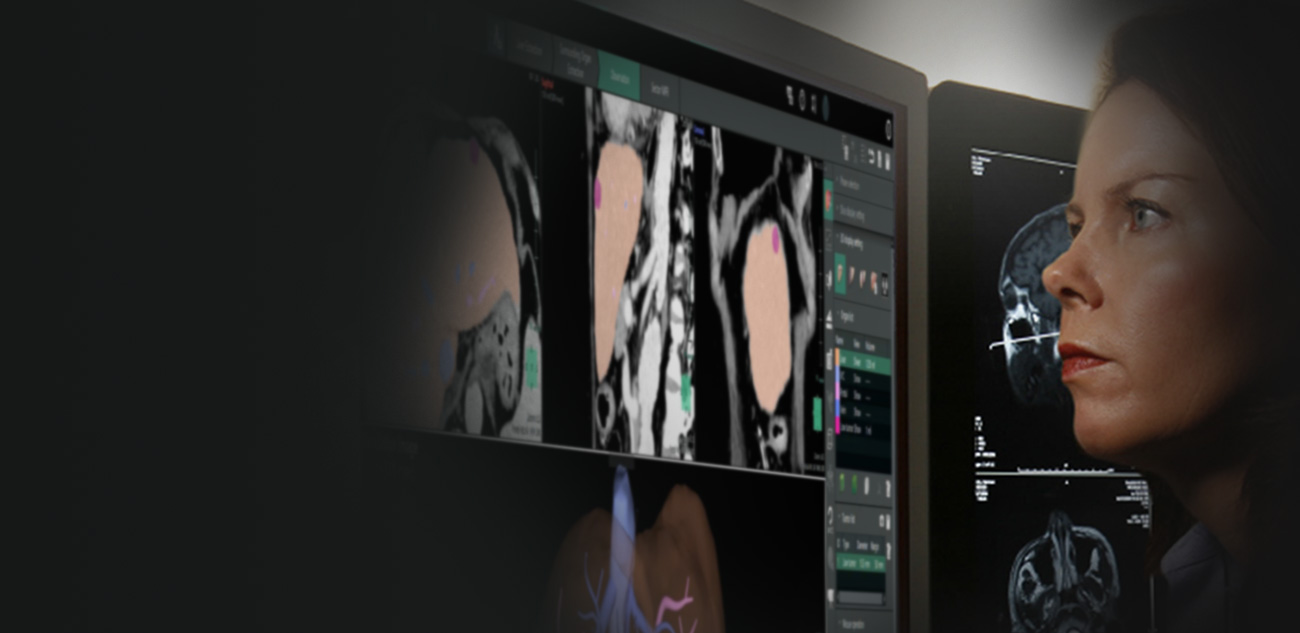

- Vincent is a planning software that allows you to easily and quickly consider the surgical approach method for your patients.

- Vincent simulation images bring useful three-dimensional clinical information to the surgeon.

- Advanced analysis features provide surgeons a choice of optimal and safe surgical approach.

- Simulated images can also be used for image guided surgery such as laparoscopic or robotic surgery.

- Vincent is designed for Physicians and Surgeons; with intuitive easy to use user interface, automatic organ segmentation, and integrated workflow simulations.